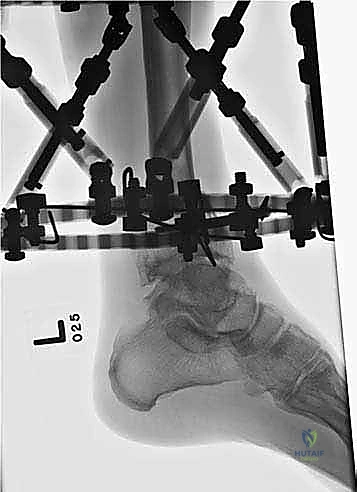

المرحلة الثانية: تركيب المثبت الخارجي (Frame Application)

قبل قطع العظم، يقوم الدكتور هطيف بتركيب الهيكل الخارجي (الإليزاروف أو الفريم الدائري).

1. يتم إدخال أسلاك دقيقة جداً (K-wires) ومسامير نصفية (Half-pins) عبر الجلد إلى العظم بدقة متناهية لتجنب الأعصاب والأوعية الدموية.

2. يتم تثبيت هذه الأسلاك في الحلقات المعدنية الخارجية. حلقة أو حلقتين فوق مكان القطع المخطط له، وحلقة تحته (في الجزء السفلي من الساق والقدم إذا لزم الأمر).

3. يتم التأكد من استقرار الهيكل الخارجي بالكامل.